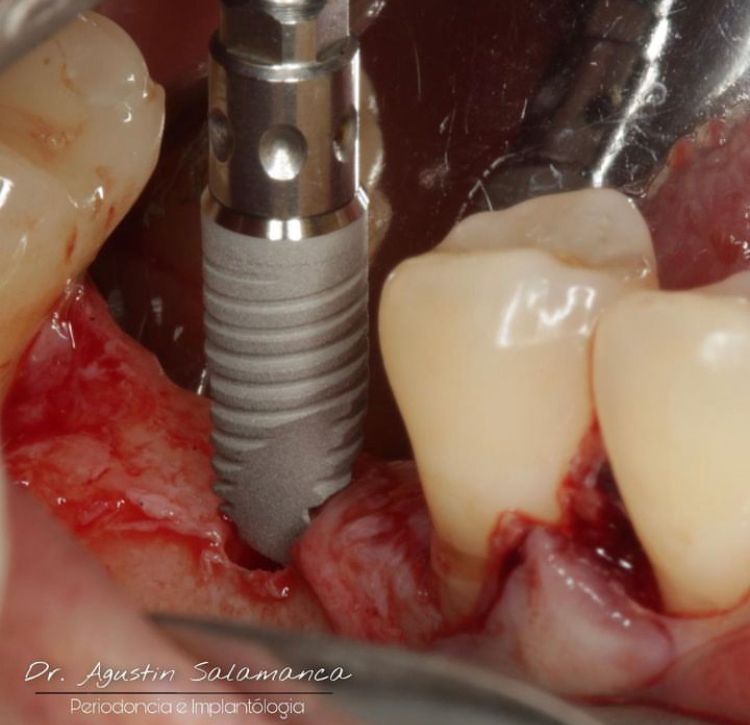

Dr. Agustin Salamanca Tapia

Fotos y videos

¿Que es un Implante Dental?

- Es un aditamento con forma de tornillo elaborado de titanio o de zirconio, que se inserta en el hueso a través de una pequeña cirugía, hasta que se osteointegre con el hueso y se coloque un provisional y posteriormente una corona definitiva.

-La ventaja de los Implantes Dentales es que sustituyen a los dientes o muelas perdidos sin que se tenga que desgastar los dientes adyacentes para un puente fijo.